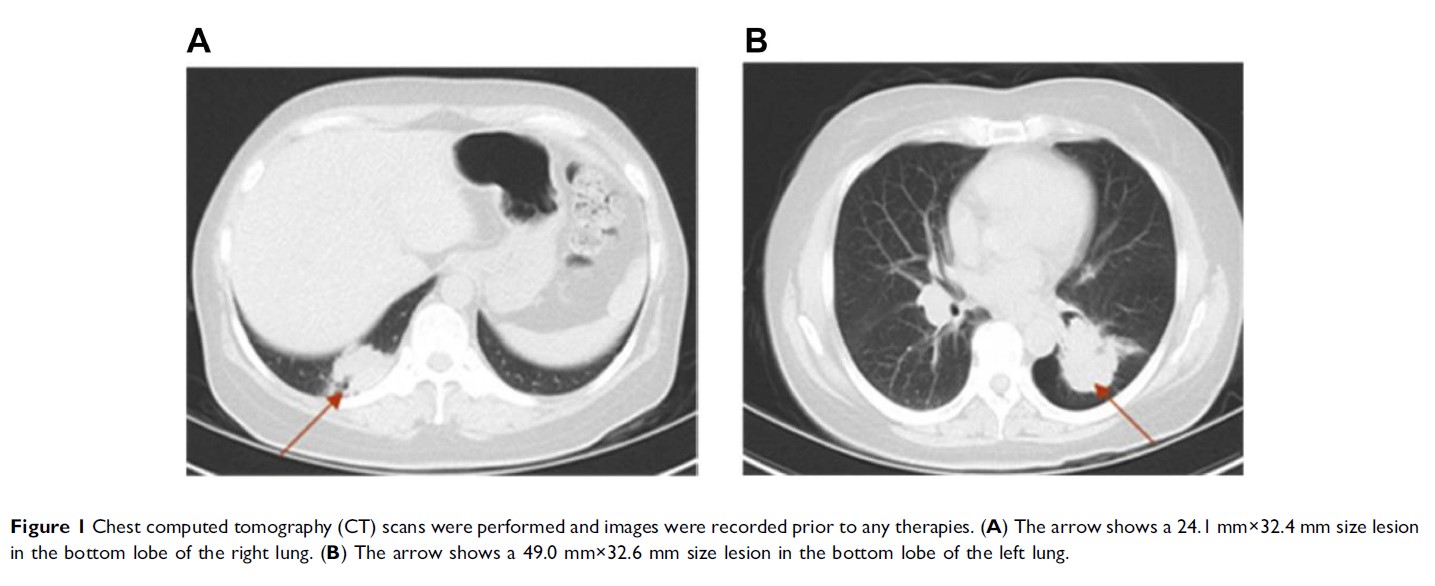

Case Report

同期多原发肺癌的诊断和治疗 - 病例报告